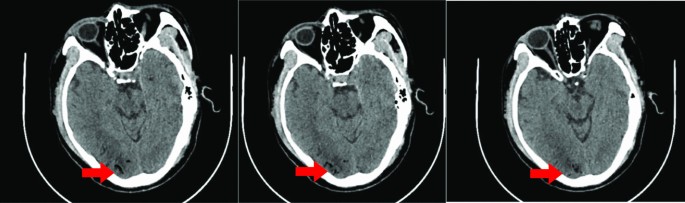

General anesthesia was induced and maintained according to standard protocols during surgical preparation. Then right pneumonectomy was performed, and the surgical incision was located at the posterolateral side of the fourth intercostal space. The pulmonary artery, pulmonary vein and bronchus were cut off with a stapler, with intraoperative bleeding of about 100 ml. After the operation, the thoracic drainage tube was clamped, and the patient returned to the ward after waking up. Three hours after the operation was completed, the patient suddenly lost consciousness while sitting in bed chatting with his wife. The patient’s blood pressure was low (76/53 mmHg), and the indexes of heart rate, respiration and oxygen saturation were normal. After opening the thoracic drainage tube, a small amount of tension gas and 200 ml of bloody fluid was discharged. We immediately performed CT examination and excluded brain lesions. CT examination showed that there was a large amount of gas in the tissue space between the chest and neck (Fig. 2). Blood clots accumulated in the thoracic cavity, and CT angiography showed no abnormalities in the major cerebral arteries (Fig. 3). However, multiple free air can be seen in the blood vessels of bilateral frontal sulcus (Fig. 4). In addition to free air, suspicious cerebral infarction was also seen in the right occipital lobe (Fig. 5). It is presumed that air entering the cerebral circulation led to air embolism. The patient had seizures soon after the CT scan, manifesting as binocular gaze and tremor of limbs. Then the patient was quickly transferred to ICU. Respiratory assistance, mannitol dehydration and empiric antibiotic treatment were used after ICU transfer. 800 ml pleural fluid was drained from the thoracic cavity 6 h after the operation, and a second thoracotomy was performed to stop bleeding. Then blood clot was removed from the thoracic cavity. After the operation, the patient was sent back to the ICU for ventilator-assisted breathing, and the head was protected by mild hypothermia using an ice blanket to prevent excessive brain damage. At the same time, mannitol dehydration was used to reduce brain edema and anti-infection treatment was carried out. On the next day, the brain CT showed a significant decrease of air in the brain (Fig. 6). There was no significant increase in cerebral infarction lesions compared with the first day. After 3 days of ventilator-assisted breathing, the patient’s condition gradually improved. On the third day after air embolism, the brain CT was reexamined. There were patchy low density areas in bilateral thalamic basal ganglia, temporal lobe and occipital lobe, which was cerebral infarction lesions. The patient was discharged after 25 days of treatment after cerebral infarction. He was conscious at the time of discharge, with neurological impairment symptoms of bilateral in which symptoms of left limb are more serious. The process from onset to recovery was smooth. After 3 months of follow-up, most of the neurological deficit symptoms had been recovered except for the left upper limb (Fig. 7).